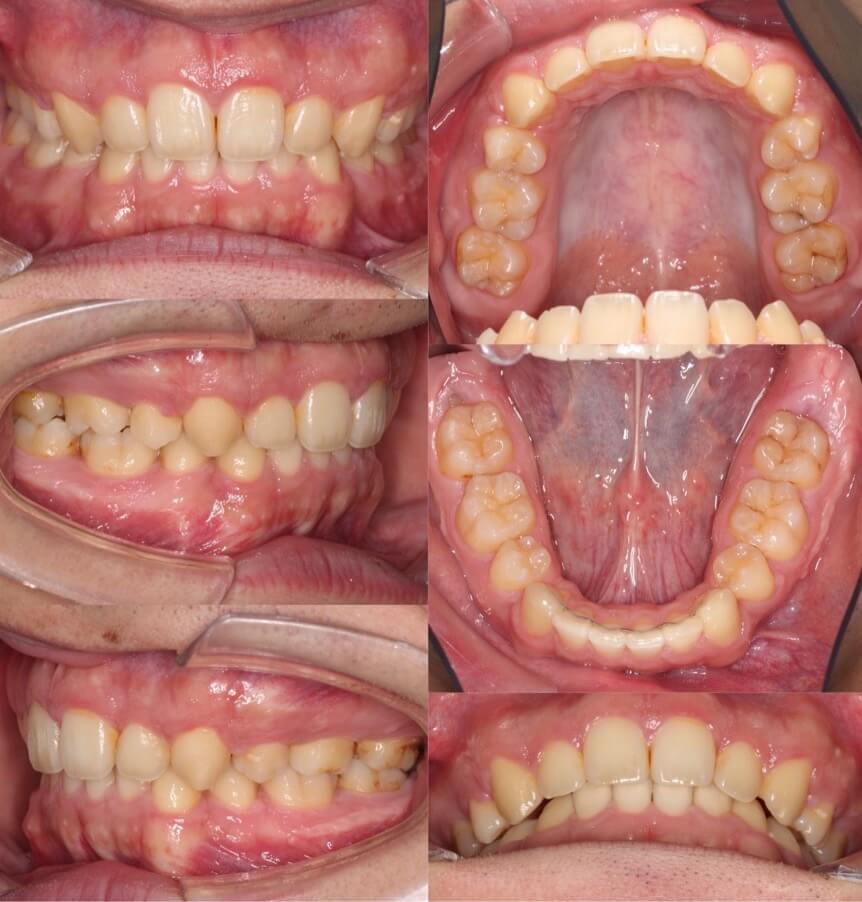

典型的なII級2類と呼ばれる、過蓋咬合を伴う上顎前突症例です。10代前半であり下あごのかみ合わせがまだ定まっていなかったため、バイトウィングという下あごの前後的位置を調整するマウスピースを使用をして正しいかみ合わせに調整しました。内側に倒れていた上の前歯の向きも改善し、良いスマイルに変化しました。

<症例概要>

主訴:歯並びのがたつき

住まい:千葉県船橋市

年齢・性別:中学生女子

症状:上顎前歯舌側傾斜・過蓋咬合・上下顎叢生・アングルII級2類

治療方針:上顎前歯の前方傾斜移動・下顎の前方推進

治療装置:マウスピース型矯正装置(アライナー装置)

治療期間:1年11か月

アライナー枚数:36+38+27ステージ (7日交換)

リテーナー:上下フィックスタイプ+プレートタイプ

治療費用:990,000(税込)

代表的副作用:痛み・治療後の後戻り・歯根吸収・歯髄壊死・歯肉退縮